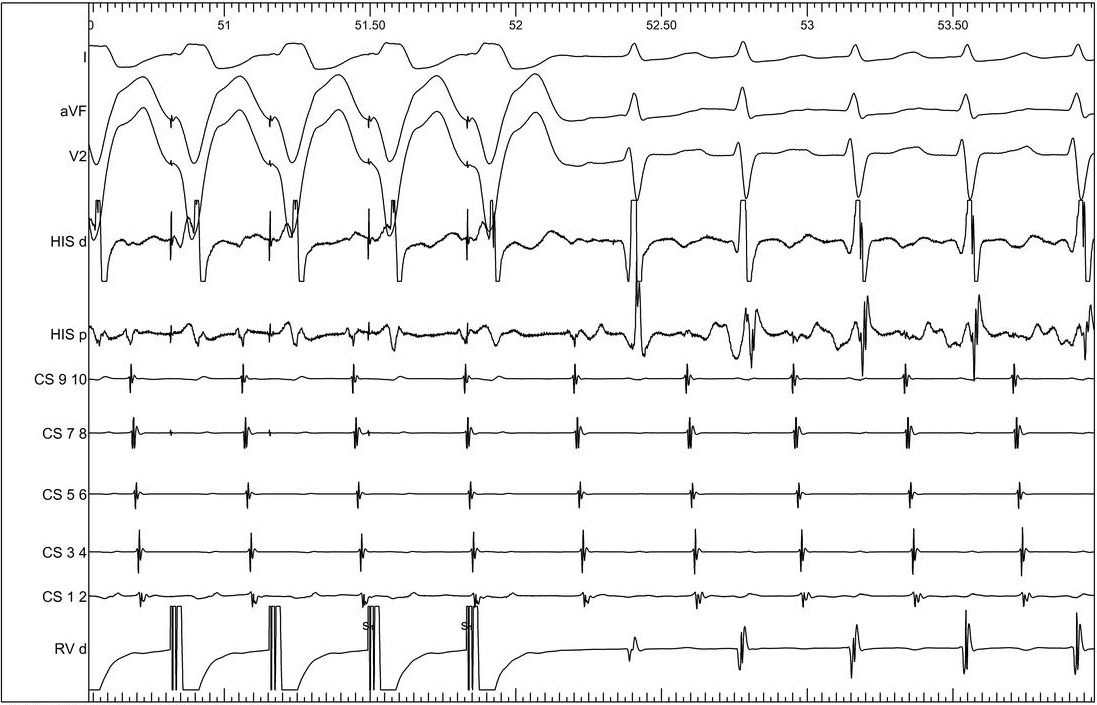

RV overdrive pacing

08_v_pace_does_not_entrain.jpg